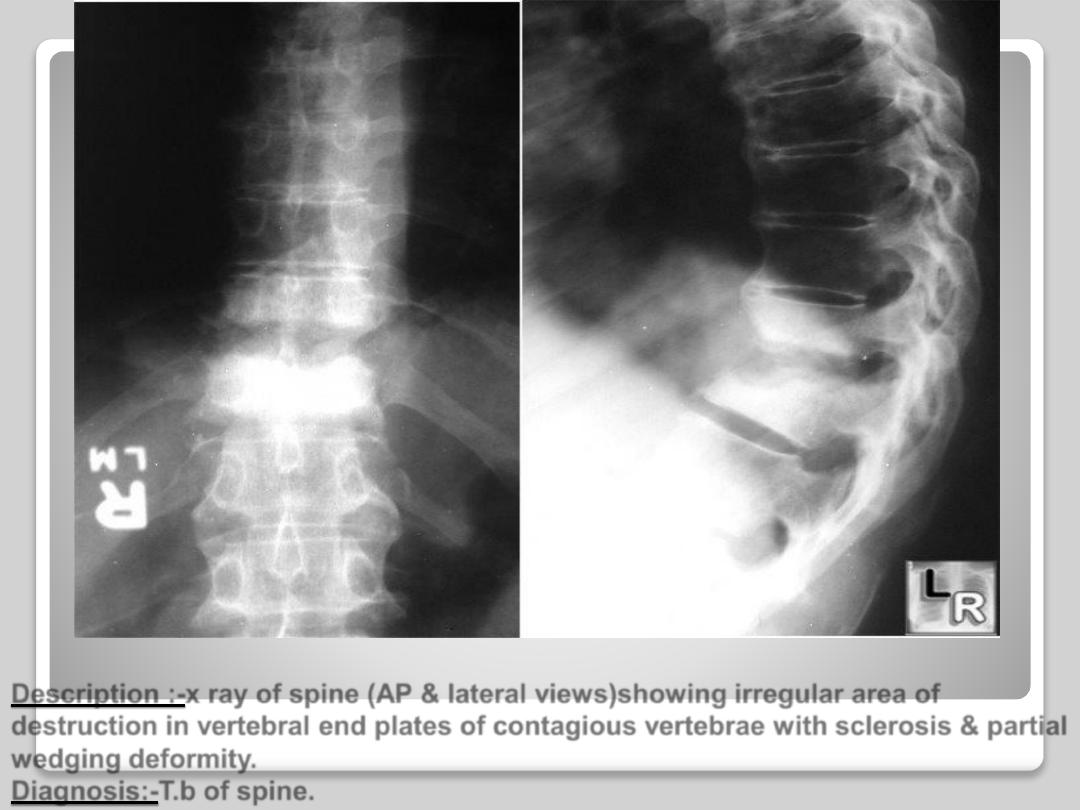

Description :-x ray of spine (AP & lateral views)showing irregular area of

destruction in vertebral end plates of contagious vertebrae with sclerosis & partial

wedging deformity.

Diagnosis:-T.b of spine.